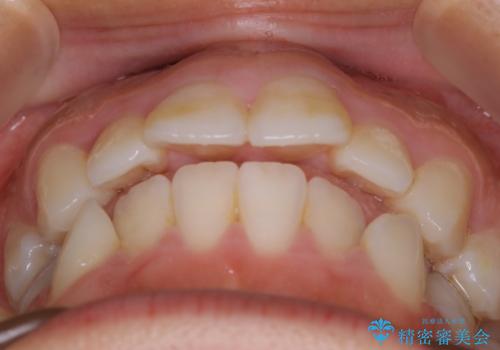

- 口元を下げたいという主訴でご来院されました。

ガタつきの度合いは軽度でしたが歯列の幅が狭く、その分前歯が上下とも前方に出てしまっていました。

しっかりと口元・顔貌まで変化を起こせるように上下左右の第一小臼歯を抜歯し、ワイヤー装置にて矯正を開始することとなりました。